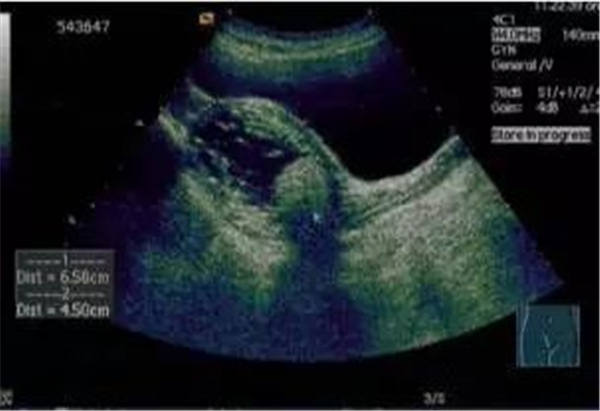

作为最特异的超声心动图特征,当右室/左室前后径比值 > 0.5;右室/左室横径(右房/左房横径)比值 >1.1或者左心室收缩末期和舒张末期径均减小,尤以舒张末期为著时,即可判定血栓性肺栓塞症。